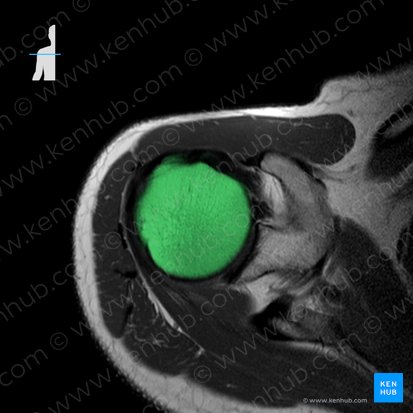

Auf dem axialen T1- oder PD-Bild auf Ebene des oberen Anteils der Art. glenohumeralis lässt sich der Humeruskopf als weiße, hyperintense Struktur erkennen. Man sieht auf derselben Ebene auch eine weiße, dreiecksförmige Struktur. Das ist der Processus glenoideus. Auf diesem Processus befindet sich die Fossa glenoidea, eine konkave Fläche, die an ihrer inferiomedialen Seite mit dem Humeruskopf artikuliert. Beide Strukturen werden durch eine dicke Knorpelschicht voneinander getrennt.